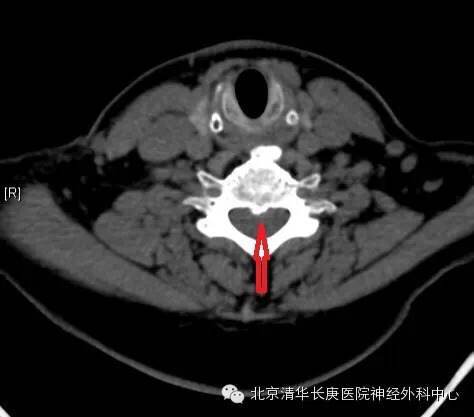

CT显示:C5-6,6-7椎间盘突出,后纵韧带骨化

术中O-ARM及导航联合精准定位及内固定